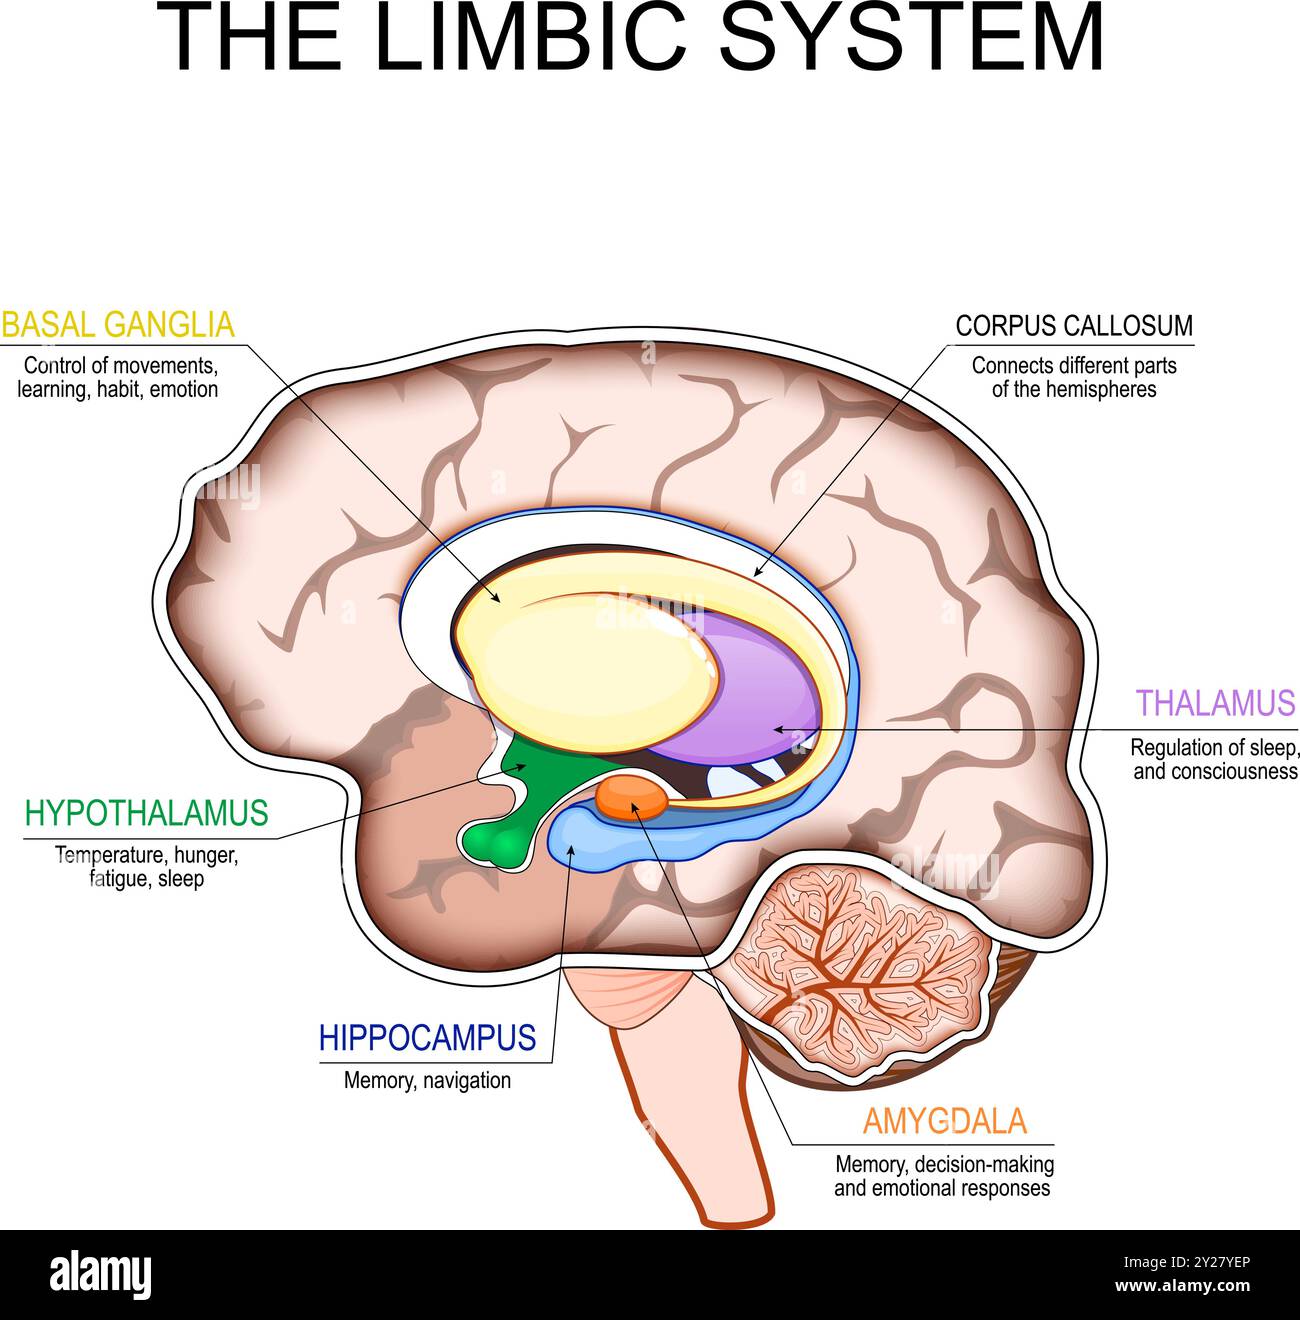

RF2Y27YEP–Sistema limbico. Sezione trasversale di un cervello umano. Corpo mammillare, gangli basali, ghiandola ipofisaria, amigdala, ippocampo, talamo, giro cingolato, corp